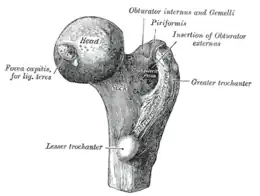

Terminaison

Le muscle piriforme se termine par un tendon qui s'insère sur le bord supérieur du grand trochanter.

Sacrum, face antérieure. Extrémité supérieure du fémur vue d'en dedans.

Extrémité supérieure du fémur vue d'en dedans. Fémur droit.Vue antérieure.